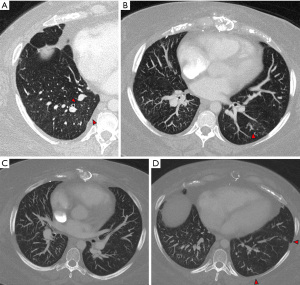

V/Q scintigraphy remains the initial test of choice for diagnosis of CTEPH. Ease of availability, extensive validation and high sensitivity are some of the obvious advantages that make V/Q scanning a robust tool for diagnosis of CTEPH (7). Early studies have shown that V/Q scanning is more sensitive than CTA in diagnosis of CTEPH (7). While this might have changed over the years with newer and improved CT scanning tools, there is no doubt that V/Q scan offers a quick way to diagnose CTEPH. Typically characterized by large, mismatched perfusion defects, a normal scan effectively rules out CTEPH. V/Q scan is not without limitations and false positive defects can be seen with numerous other conditions such as vasculitis, fibrosing mediastinitis and neoplastic lesions such as sarcoma. In one study on 150 patients comparing various V/Q scanning techniques with CTA (9), both V/Q scanning techniques were more sensitive [V/Q single-photon emission computed tomography (SPECT): 85%, P<0.001 vs. CTA: 67%; V/Q planar scintigraphy: 83%, P<0.001 vs. CTA: 67%], and less specific (V/Q planar scintigraphy: 51%, P=0.03 vs. CTA: 60%; V/Q SPECT: 42%, P<0.01 vs. CTA: 60%) than was CTA for segmental analysis. Poor subpleural perfusion (PSP) in the capillary phase of pulmonary angiography is considered one of the direct imaging signs of underlying SVD (10) (Figure 2). This finding can be evaluated with V/Q scanning although can be limited with planar imaging due to shine-through effect as well as due to limitations in spatial resolution. As noted above, SVD is suspected in patients with discordant imaging and hemodynamic findings. This has also been shown with V/Q scanning; in one study on 76 patients, it was shown that CTEPH patients had higher mean pulmonary arterial pressure (mPAP) and total pulmonary resistance (TPR) as compared to patients with acute PE for similar degrees of vascular obstruction as measured on V/Q scanning (11). Another longitudinal analysis of V/Q scans in patients with unoperated CTEPH has shown that the classic findings of segmental mismatched perfusion defects change progressively over time and evolve into a more homogenous perfusion pattern, something that can be attributed to development of secondary microvasculopathy (12).

CTA is an established frontline imaging in evaluation of CTEPH. Excellent spatial resolution, high contrast-to-noise ratio, and detailed assessment of pulmonary arteries down to the subsegmental levels are some of the advantages that make CTA a premier tool in evaluation of CTEPH. Another advantage of CTA is the ability to simultaneously evaluate alternate causes of perfusion defects, thus limiting the differential diagnoses. CTA is the test of choice for anatomic mapping of disease and characterization of CTEPH lesions, which can help in surgical planning or targeting lesions for BPA. One of the limitations of CTA is that CTEPH lesions can be subtle and can be missed if not carefully evaluated; this has accounted for lower sensitivity of CTA in CTEPH detection as compared to V/Q scanning (9). CTA offers several insights into evaluation of SVD, although none are specific. One of the commonly used marker is the presence of mosaic attenuation. This is a nonspecific finding in isolation, although associated findings such as segmental vessel caliber reduction, presence of bronchial artery and systemic collaterals and parenchymal densities point to CTEPH as likely cause (13) (Figure 3). In context of CTEPH, mosaic attenuation also termed as “mosaic perfusion” refers to patchwork of increased CT attenuation (reflecting redistributed vascular flow) and decreased CT attenuation (which are areas of obstructed vessels or microvessel disease). Newer tools such as photon counting CT can provide further insights into evaluation of mosaic perfusion. In a small study on 29 CTEPH patients with mosaic perfusion evaluated with photon counting CT (14), significant differences in the diameters of the most distal pulmonary vessels were noted with higher frequency of dilated arterioles (91.9%) and venules (70.9%) in areas of ground-glass opacity (GGO), while thin arterioles (69.8%) and venules (55.8%) were the dominant findings in areas of hypoattenuation. In areas of GGO, findings similar to Group 1 PH were seen such as ill-defined micronodules, and areas of lobular GGO. Systemic-to-pulmonary anastomoses were depicted more frequently in the periphery of hypoattenuated areas (36%) versus hyperattenuated areas (25.6%) (Figure 3); these have been shown to be contributors to SVD (14). Presence of bronchial artery (BA) collaterals is known to be associated with a good postoperative response and likely represents a protective response in maintaining the viability of lung parenchyma distal to the PA occlusive lesions (15). In a study by Shimizu et al., total cross-sectional area of BA measured with CTA correlated with extent of central disease, and the area was significantly higher than in patients with distal microvascular disease (16). Quantitative CTA assessment of small vessels can provide functional insights for CTEPH patients and might help identify patients with SVD, although data is sparse. Shahin et al. evaluated different subgroups of PH using quantitative CT and found that patients with CTEPH had reduced volume of peel vessels and small vessel volume correlated with pulmonary function tests (17).